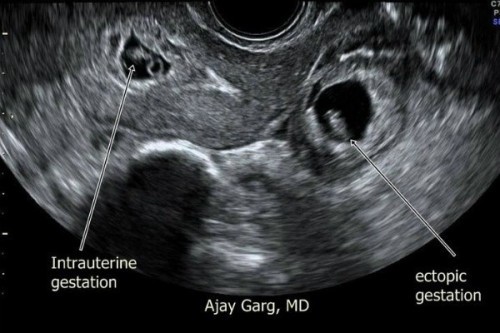

Mengandung Luar Rahim?

Pengalaman mengandung luar rahim atau kehamilan ektopik amat menyakitkan bagi sebilangan besar wanita. Namun apakah penyebab dan risiko ia terjadi? Info lanjut: https://my.theasianparent.com/pengalaman-mengandung-luar-rahim